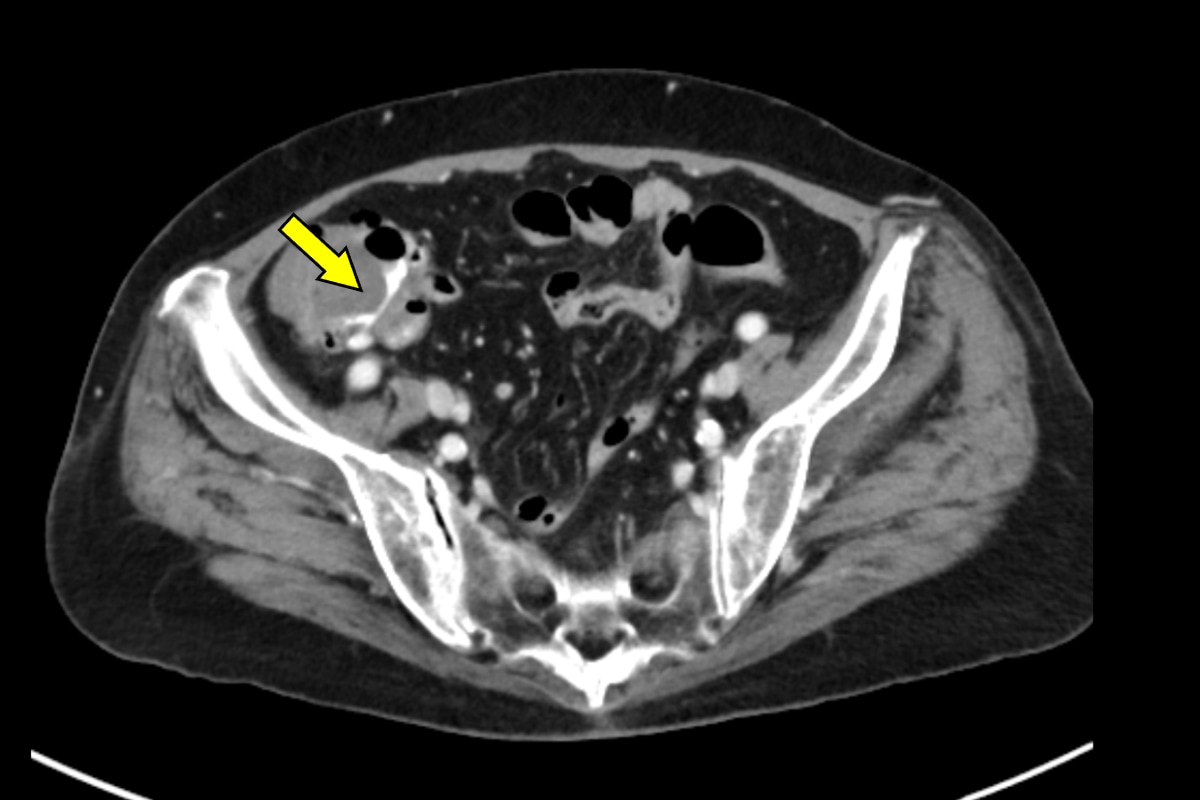

血便があり、当院消化器内科に入院となった。第3病日に下部消化管内視鏡を行うも出血源は不明であった。第4病日に再度血便があり、造影CTを施行すると上行結腸憩室からの活動性出血を認めたため、速やかに緊急TAEを施行した。血管造影で回結腸動脈の分枝からextravasationを認め、責任動脈をコイル塞栓した。術後、再出血、Hb値の低下を認めず、第13病日に退院となった。

消化管出血では出血源を迅速かつ正確に同定することが診療上、不可欠である。内視鏡は有用であるものの、腸管の前処置を要し、観察に時間を要する他、出血が間欠的であれば診断が困難となる場合がある。これに対して造影CTは、非侵襲的かつ短時間で活動性出血の有無と局在を明確に描出できる。活動性出血があれば、動脈相から腸管内への造影剤の漏出を認め、静脈相や遅延相ではその造影剤漏出の拡大を確認することで、客観的に活動性出血を診断できる。さらに、造影CTで得られた情報に基づき責任血管を同定することで、後続の血管造影検査の効率が高まり、速やかに経カテーテル的動脈塞栓術(TAE)へと移行できる。当院では、造影CTで活動性出血が確認された結腸憩室出血に対して速やかにTAEを施行しており、その成功率向上に寄与している。一方で、出血が間欠的または少量の場合には描出が難しく、検査のタイミングによって診断能が左右されるという限界もある。それでも、結腸憩室出血において造影CTは診断と治療方針をつなぐ、重要な検査として位置付けられる。

本症例ではPhoton Counting CT(PCCT)を用いた。PCCTは従来型CTに比べ空間分解能とコントラスト分解能が高く、少量の造影剤でも高精細な画像を得られることが特徴である。これにより微細なextravasationやそれに連続する責任動脈の描出が可能となり、診断精度を大きく高める。

撮像プロトコルは活動性出血が疑われる場合、動脈相と平衡相の2相を基本としている。ボーラストラッキングを用いて造影剤到達を正確に把握し、動脈相でextravasationを描出し、平衡相で造影剤漏出の拡大を確認することで、出血の有無と局在を診断している。

PCCTによる高精細な画像はextravasationの検出にとどまらず、責任血管を描出することで標的血管の特定を容易にする。その結果、血管造影での探索時間が短縮され、経カテーテル動脈塞栓術(TAE)の迅速かつ確実な施行につながり、手技の成功率と効率を高めている。